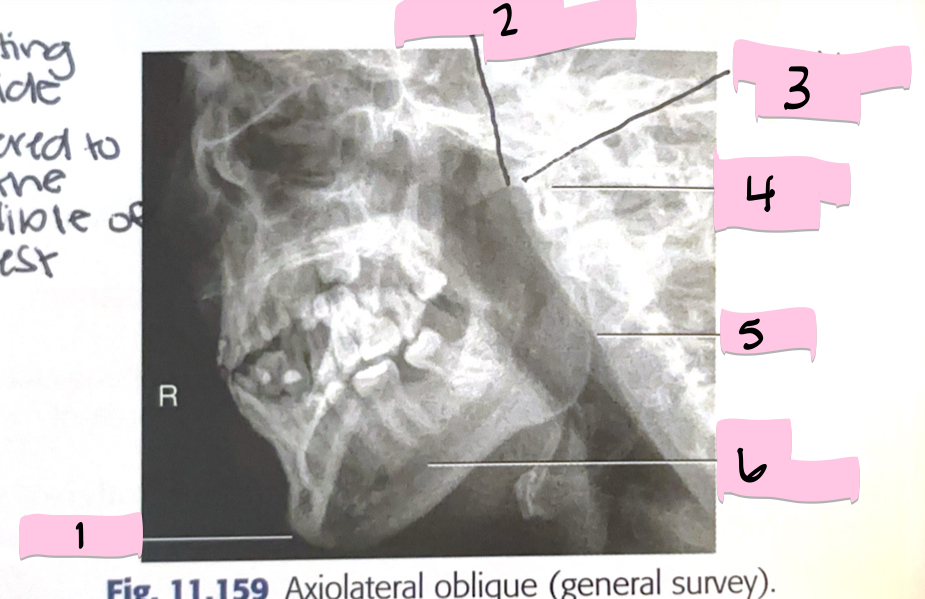

What is 1 pointing to?

Frontal sinus

What is 2 pointing to?

Superior orbital fissure

What is 3 pointing to?

Bony nasal septum

What is 4 pointing to?

Anterior nasal spine

What is 5 pointing to?

Crista galli

What is 6 pointing to?

Petrous ridge

What is 7 pointing to?

Floor of orbit

What is 8 pointing to?

Maxillary sinus